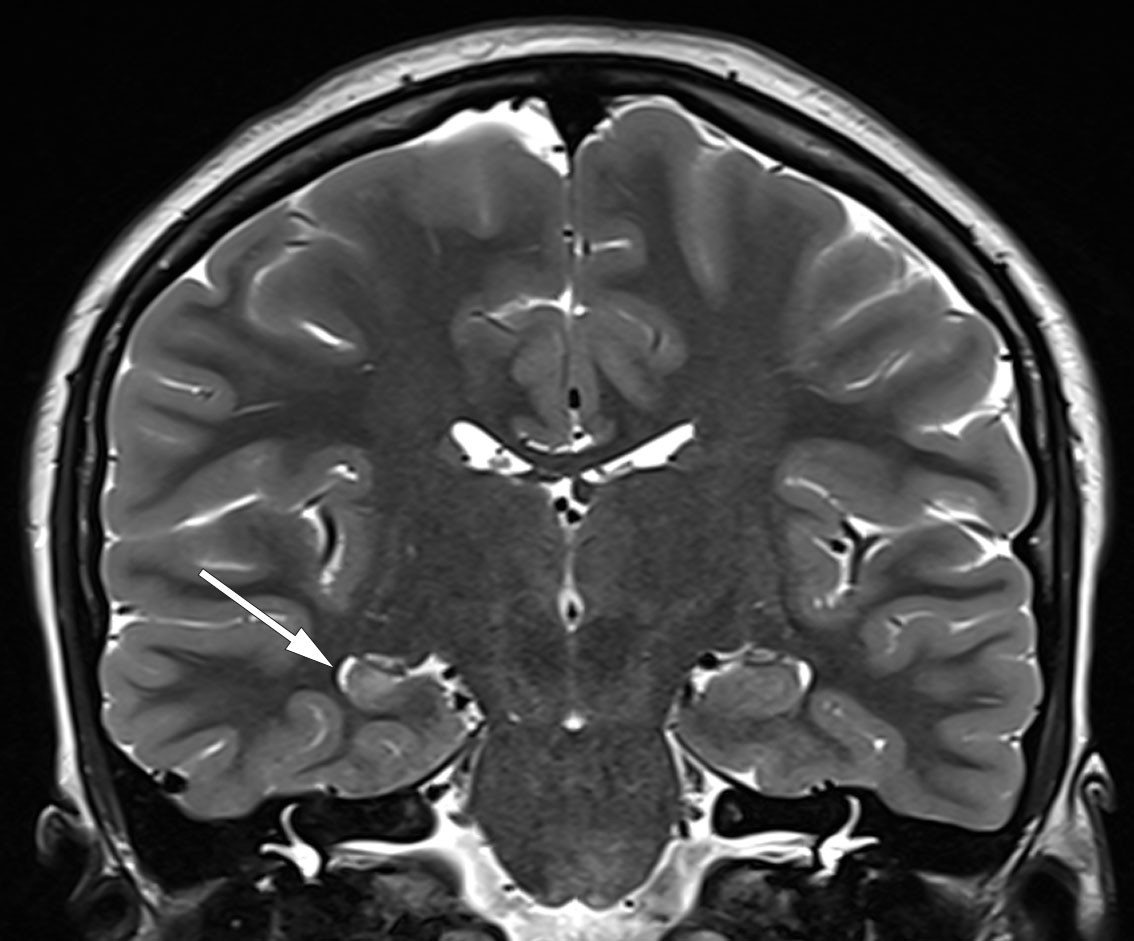

Magnetic resonance imaging (MRI) of the brain, preferably using a 3 Tesla scanner and an epilepsy protocol, reveals an epileptogenic lesion in around 70 % of this patient population (15). The lesion may, for example, be a glioma, a cortical dysplasia, or hippocampal sclerosis with atrophy of the hippocampus and increased signal intensity on T2-weighted series (Figure 2). Positron emission tomography (PET) may show hypometabolism over anterior medial areas of the affected temporal lobe.